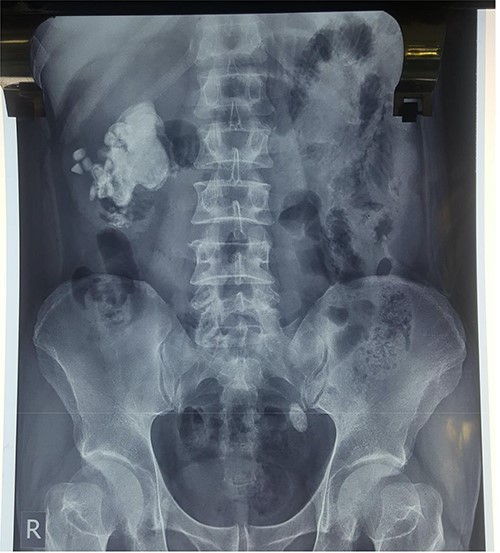

Ultrasound of the kidneys, ureters and bladder (USS KUB) revealed a 2 cm calculus in the left lower ureter with proximal hydroureteronephrosis along with an incidental giant SC, measuring ~8 cm in its largest dimension, occupying the right renal pelvicalyceal system. The SC was surrounded by multiple smaller calculi. A plain X-ray KUB confirmed these findings (Fig. 1). Because of the complexity of this case, a non-contrast computed tomography (NCCT) of the abdomen was performed to further demarcate the anatomy for perioperative planning (Fig. 2a and b).

Plain X-ray KUB displaying a giant right-sided staghorn calculus surrounded by smaller secondary calculi along with a 2 cm calculus located in the distal third of the left ureter, at the inferior border of the sacroiliac joint.